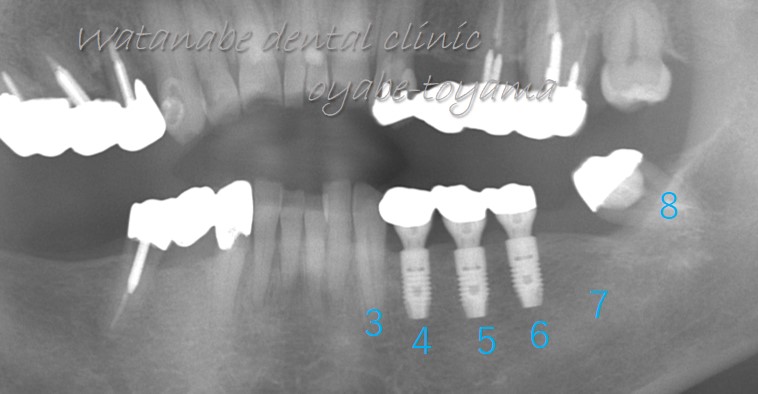

4,5,6,7と4本の歯が喪失していますので3と8を支台としたブリッジも歯の移植も不可能な状態です。そこで、インプラントを選択しました。

インプラント埋入後2年の写真です。4,5,6の位置に3本のインプラントを埋入しました。インプラント周囲の骨も喪失しておらず良好に経過しています。インプラントは「歯周病菌」に感染して「インプラント周囲炎」を起こすことがありますので、インプラント埋入後の管理が重要です。